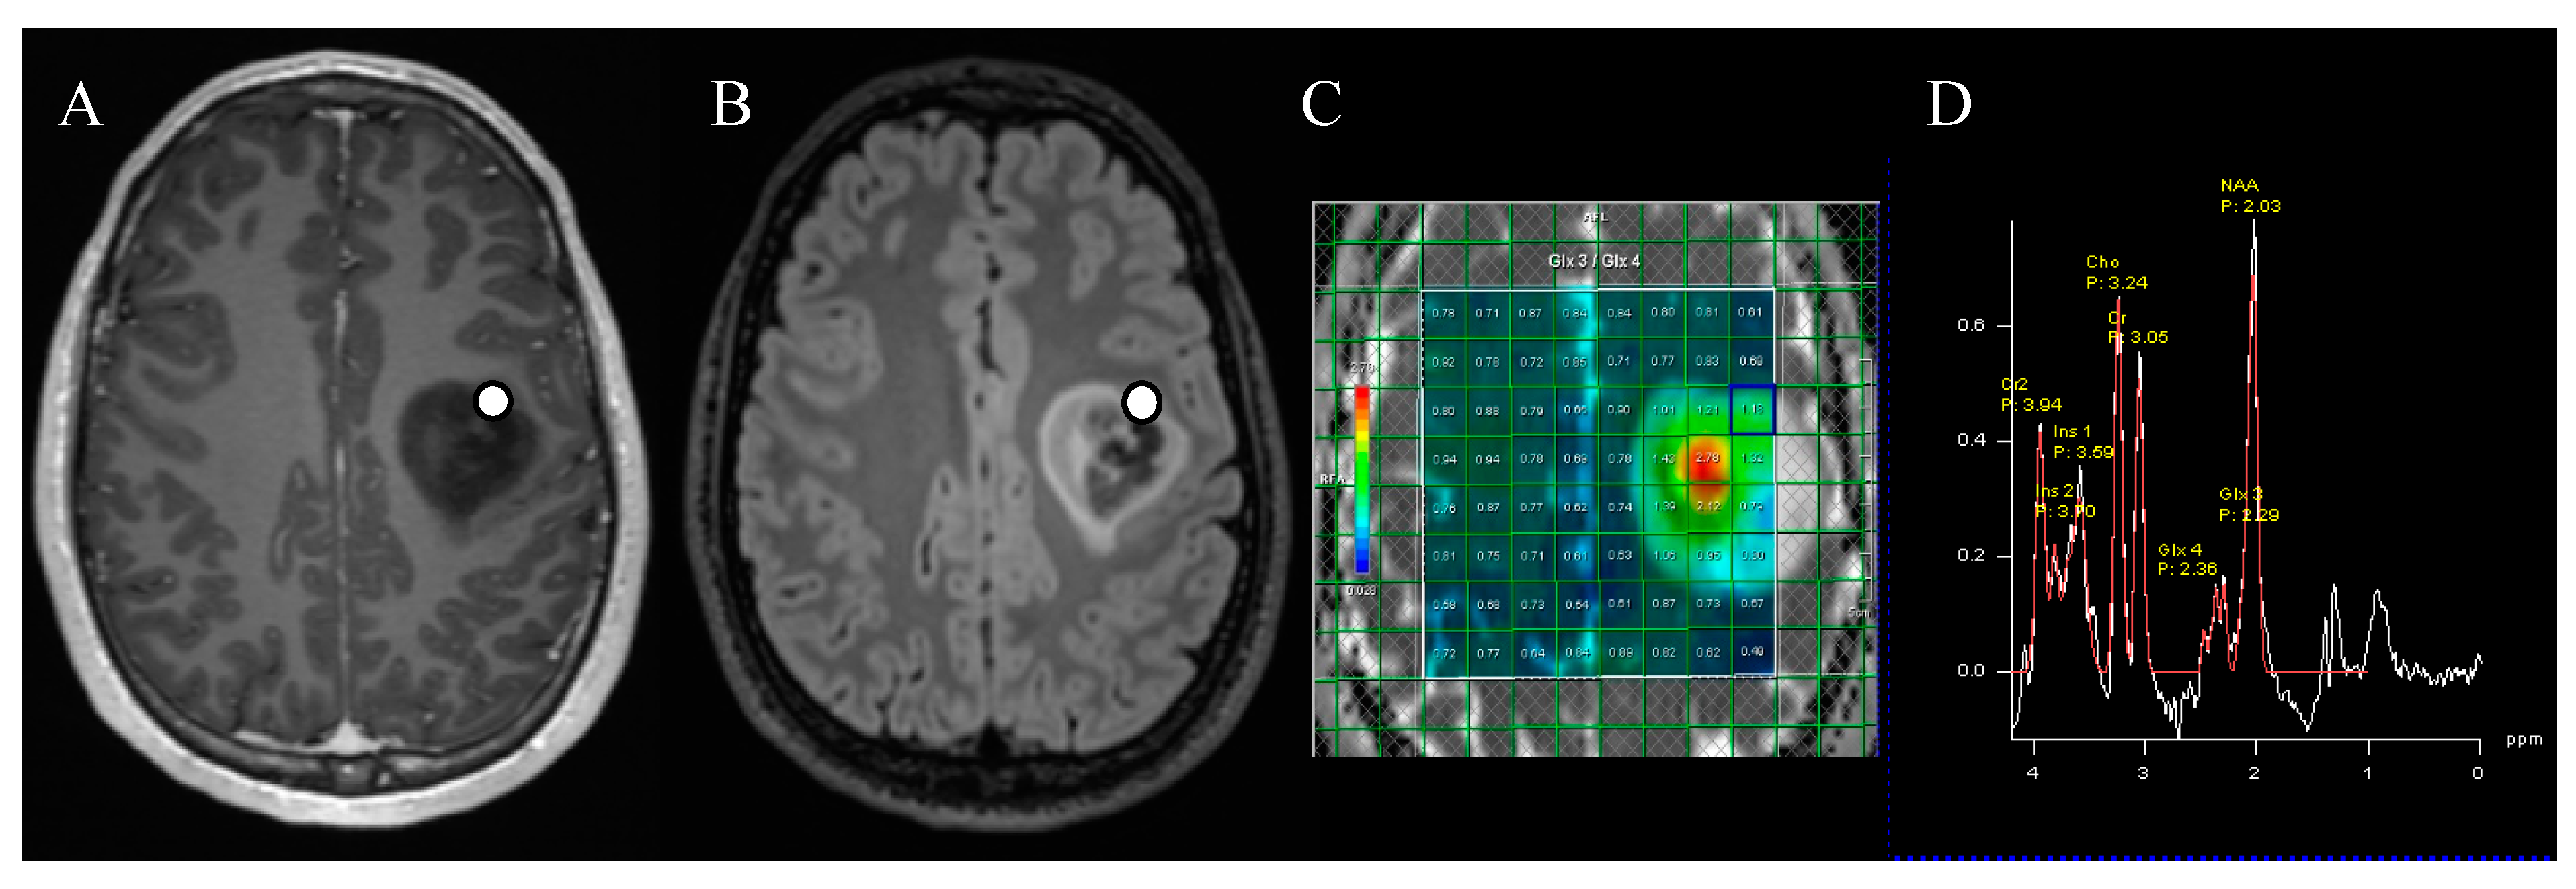

:1. Introduction

2. Methods

2.2. Scanning Protocol

2.3. MR Spectroscopy Acquisition